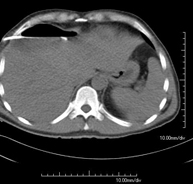

It consists of placing a drainage catheter over a collection of fluid located in the abdominal cavity, with the intention of emptying as much of the collection as possible. The patient should keep the drain in place for a few days, usually until it is no longer productive. It is often performed under sedation with the help of an anaesthesia team. The entire procedure is monitored using images obtained by computed tomography (CT) at various stages of the test, using CT fluoroscopy. After the test, the patient remains hospitalised. Coagulation tests must be performed before the test.